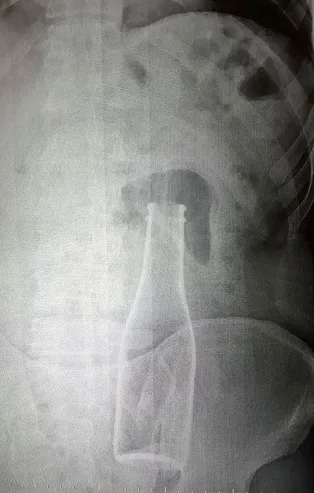

İkranur Tirsi'nin cenazesi otopsi için Trabzon Adli Tıp Kurumu'na kaldırılırken, yapılan ilk otopsisinde minik kızın ölümünde travmatik hiçbir bulguya rastlanılamazken, ciğerlerinde su dolması sonucu yani boğularak öldüğü belirlendi.